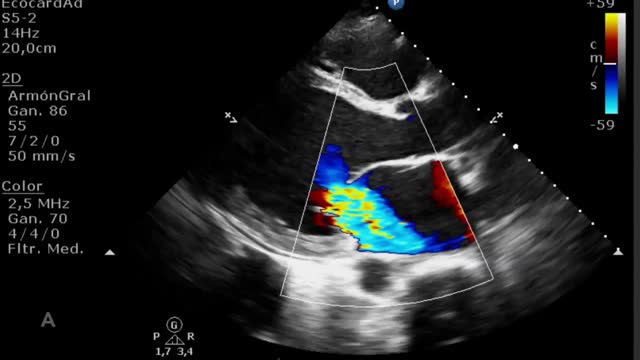

El destete supone un proceso de descenso gradual (500ml cada 15-20min) del soporte de la ECMO VA de manera que se restablece progresivamente la precarga en el corazón. Para ello el paciente debe estar adecuadamente anticoagulado. Evaluaremos la repercusión hemodinámica (PVC, PAM y diferencial, SvO2, SatO2) y ecocardiográfica (FEVI, IVT, onda E, onda E’ o S’ del anillo mitral lateral) que tiene hasta un nivel (normalmente 1-1,5l/min) que nos indique que el paciente puede tolerar la retirada de la asistencia. Durante esta, evaluaremos que mantiene e incluso aumenta la FEVI por encima del 25-30%, la IVT por encima de 10cm y la onda S’ de más de 6cm/s (fig. 5 y suplementario 22). Junto con ello, también evaluaremos el comportamiento de las cavidades derechas (desplazamiento sistólico del plano del anillo tricuspídeo>16cm, S’>10cm/s y tamaño VD) y la posible aparición de signos de hipertensión pulmonar (aumento de la velocidad pico de la insuficiencia tricuspídea) que predigan un fracaso de VD38–40.

Evaluación ecocardiográfica de destete de paciente con ECMO VA. Ecografía transtorácica e integral velocidad-tiempo (IVT) del tracto de salida del ventrículo izquierdo al reducir flujo (A: 3L/min, B: 2,5L/min, C: 2L/min) de ECMO VA. Obsérvese el aumento del tamaño de la IVT y consecuentemente del volumen sistólico y del gasto cardiaco.